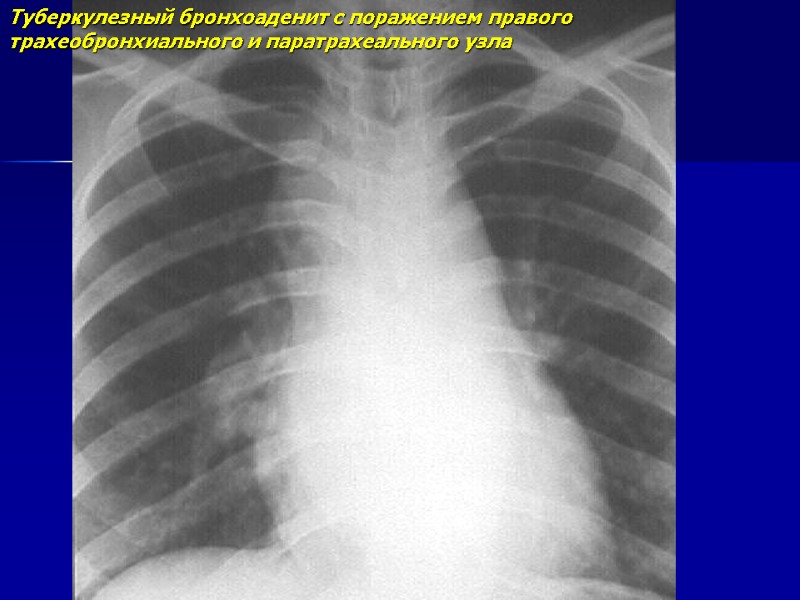

Туберкулезный бронхоаденит с поражением правого трахеобронхиального и паратрахеального узла